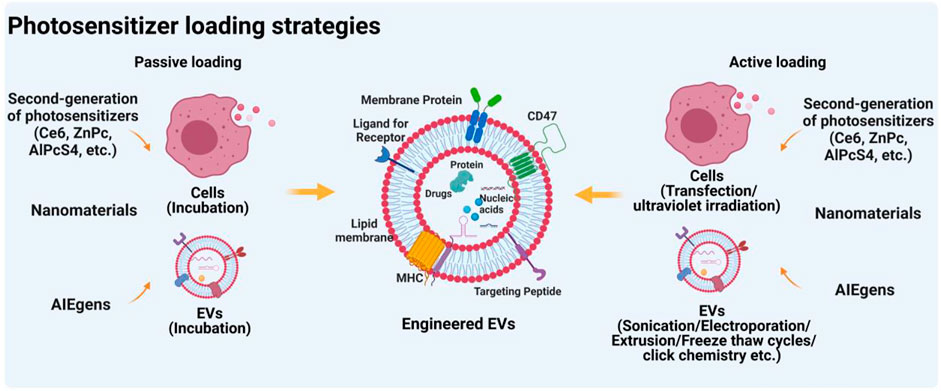

Frontiers | Extracellular vesicles as a novel photosensitive

Frontiers | Extracellular vesicles as a novel photosensitive